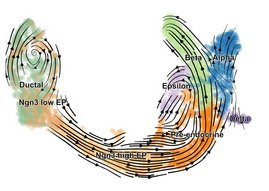

Die Erforschung der Zelldynamik ermöglicht einen tieferen Einblick in die Entstehung und Entwicklung von Zellen sowie ein besseres Verständnis von…